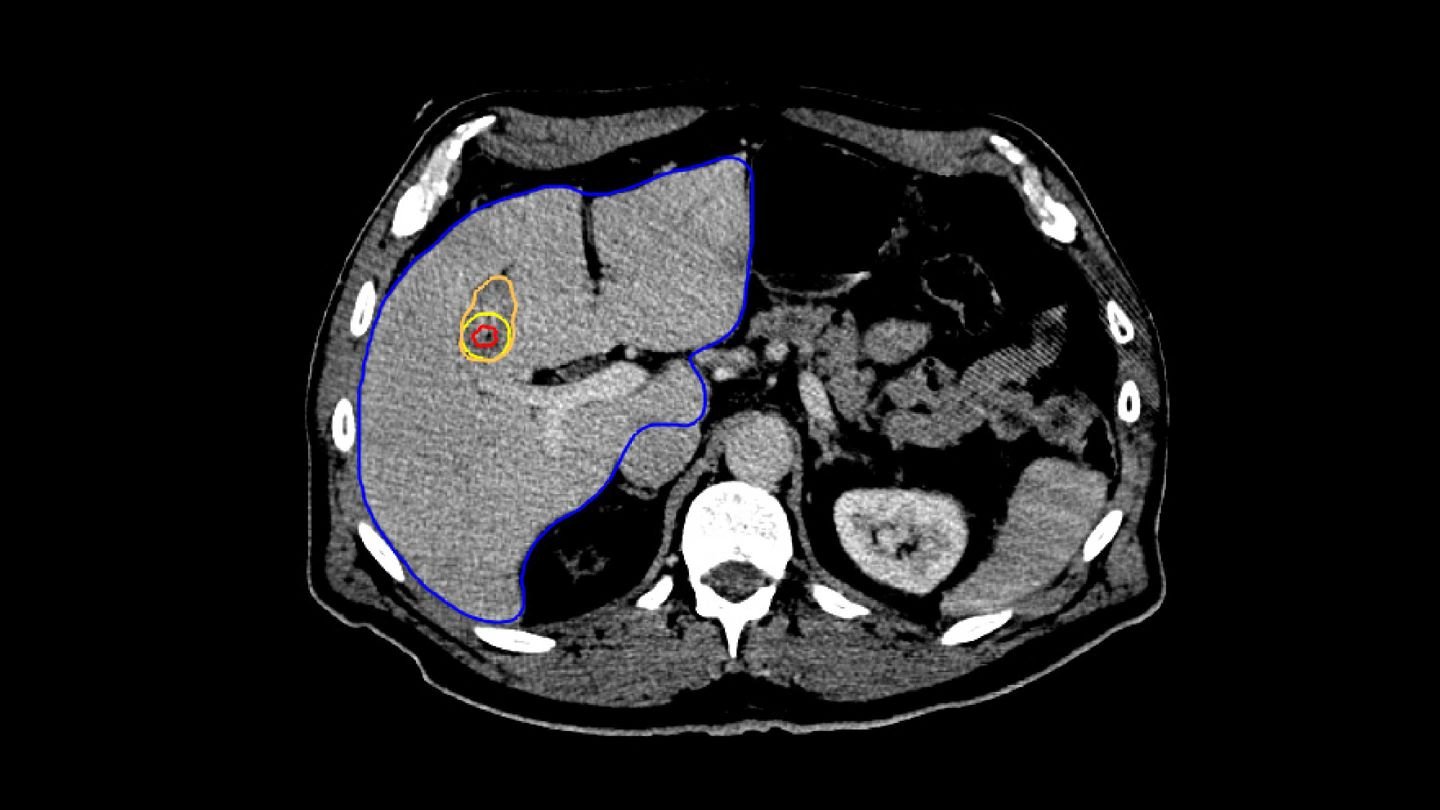

The procedure begins with the planning phase, during which the physician decides where to place the applicator. Once the location is determined, the applicator is inserted into the patient during the targeting step.

The Liver Ablation module offers tools for automatic segmentation of relevant structures. Combined with the ability to place virtual applicators and estimate the ablation zone, our software assists users to determine the optimal number of applicators and their precise placement.

To ensure accurate applicator placement before treatment, the segmented tumors from the planning phase are mapped using deformable registration, allowing for a visualization of the anticipated tumor position. Additionally, the ablation zone can be estimated based on the applicator parameters, such as its current position, selected power, and ablation duration.